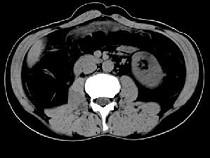

问题 女,51岁,腹胀、腹痛、进行性消瘦,影像检查如下图,最佳诊断是()

选项 A.乙状结肠Crohn病 B.乙状结肠结核 C.乙状结肠癌 D.乙状结肠淋巴瘤 E.乙状结肠息肉

答案 C